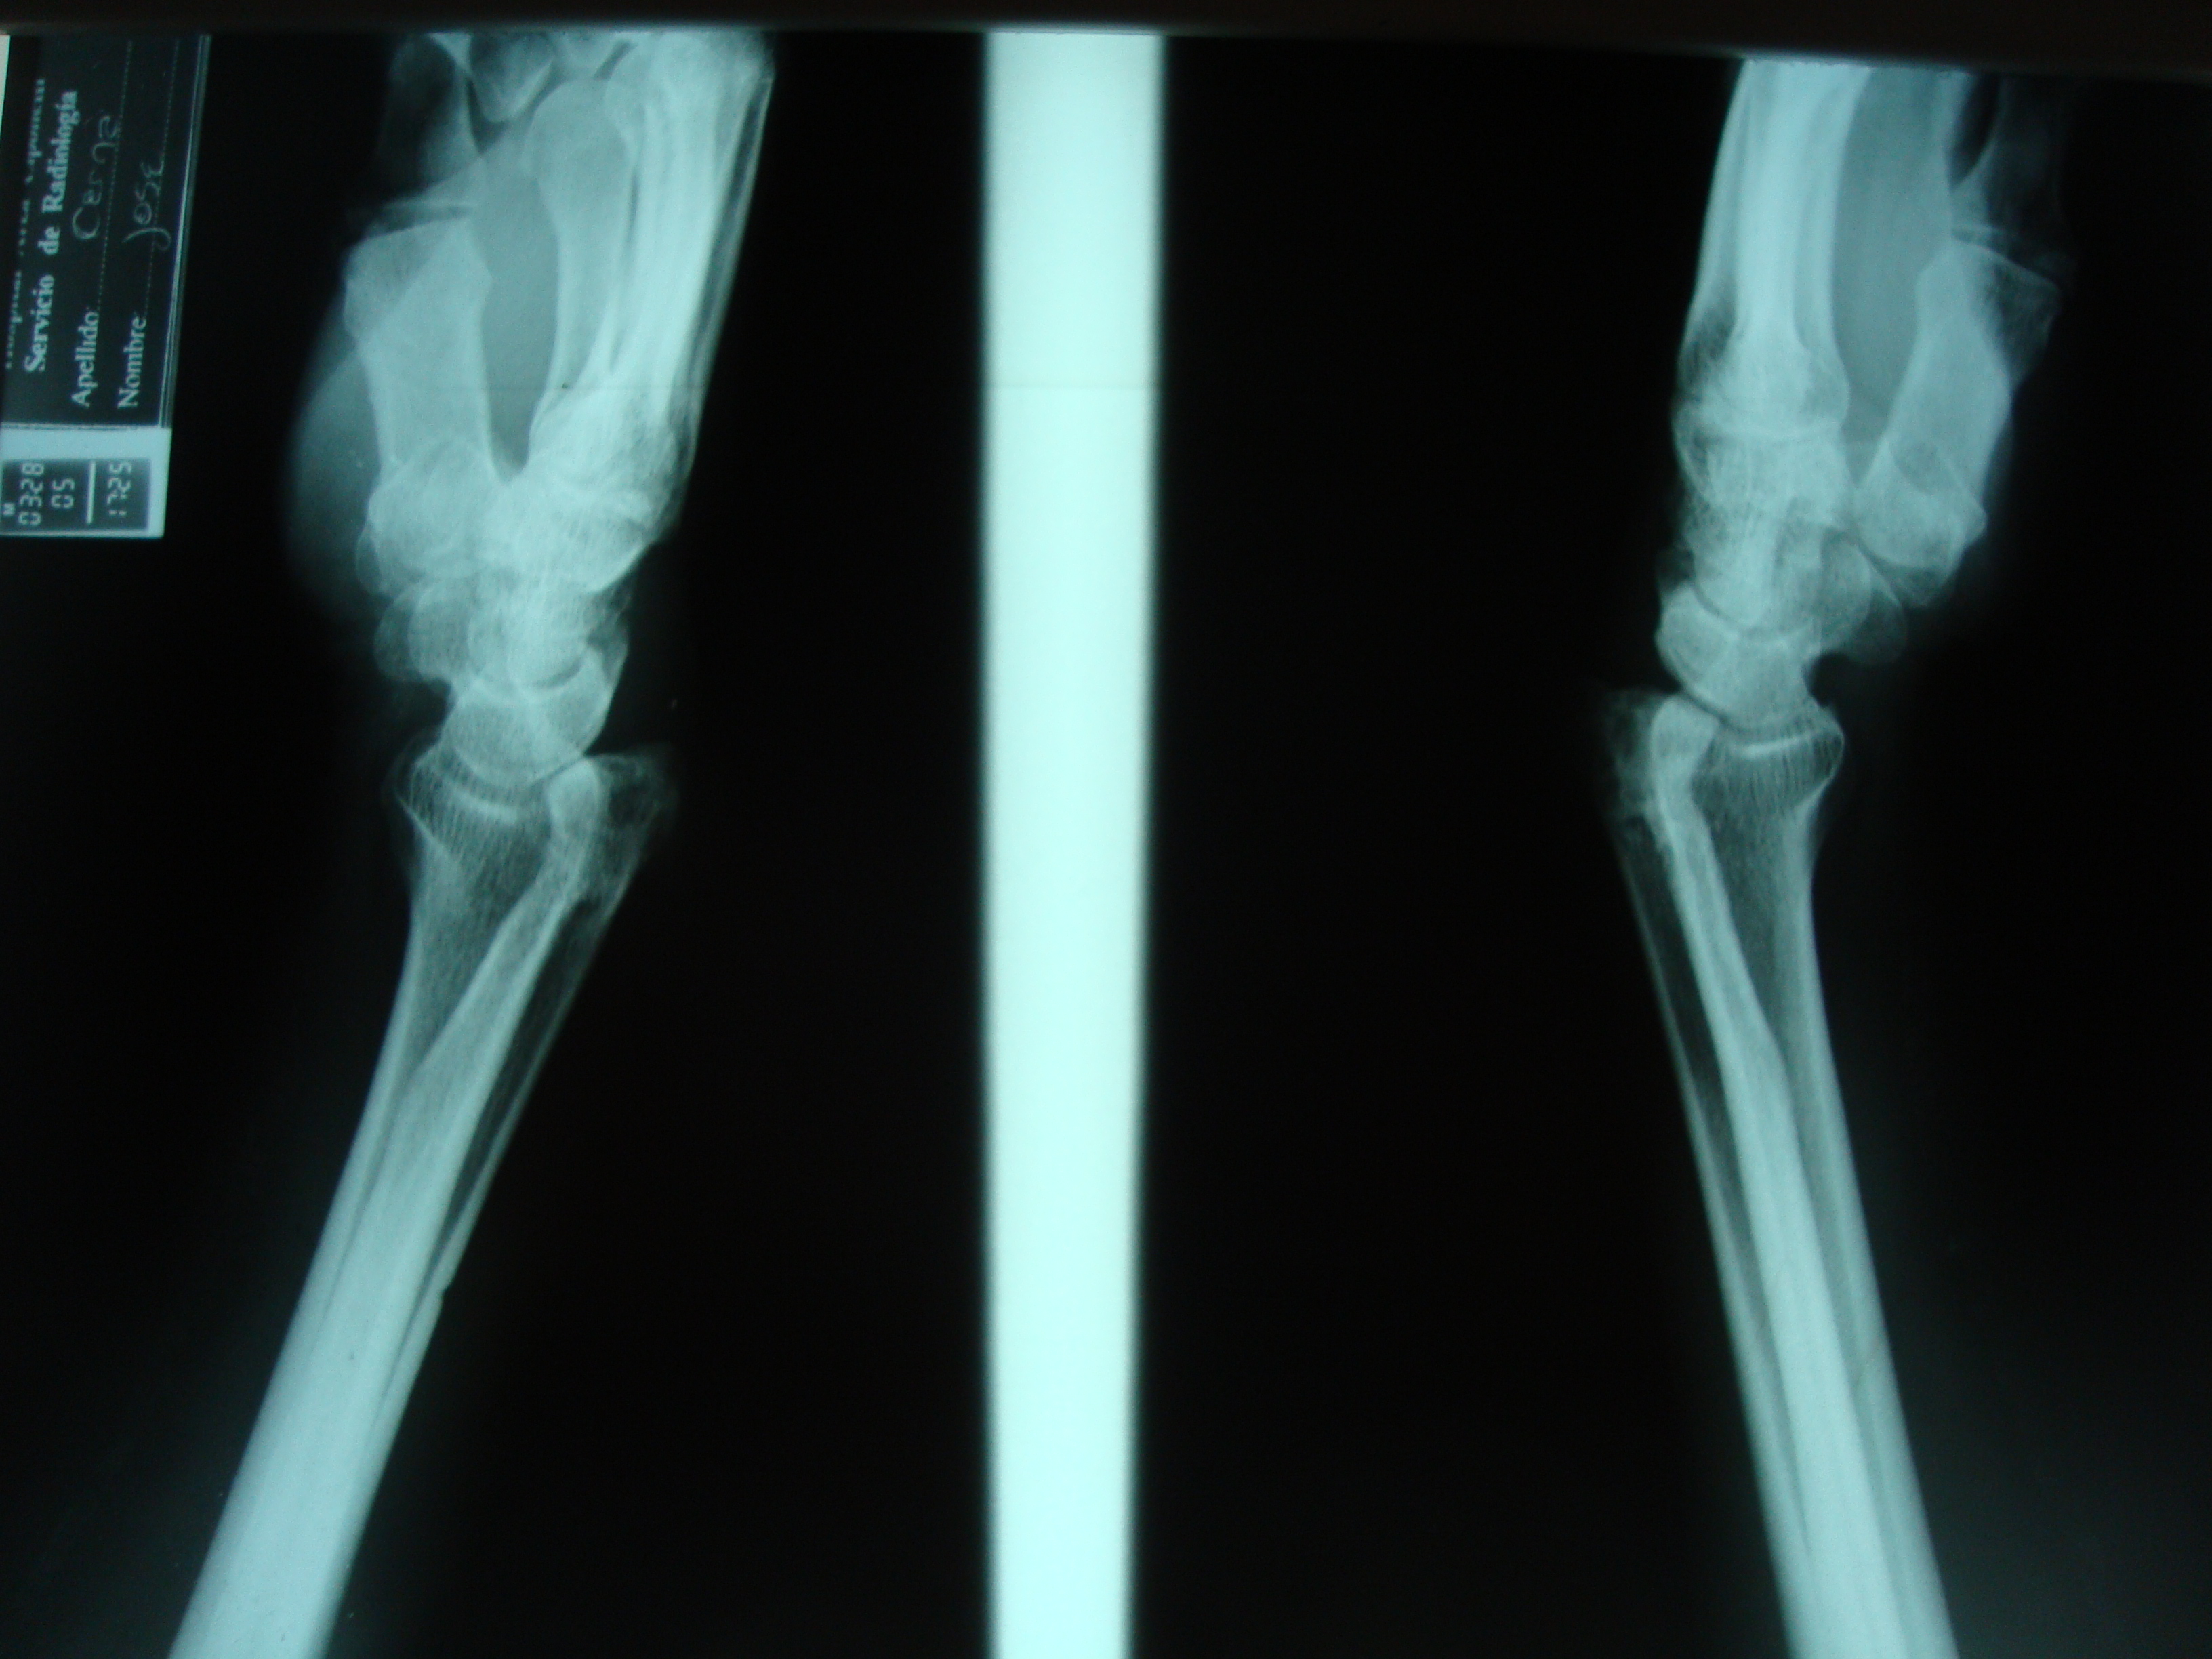

Rotura de los tendones extensores de los dedos por cúbito plus idiopático bilateral. Informe de un caso.